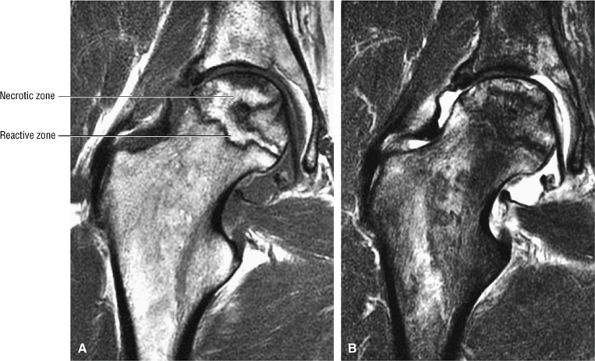

FIGURE 3.80 ● Extended pattern of marrow edema in association with osteonecrosis. Edema of the femoral neck is hypointense on T1-weighted image (A) and hyperintense on FS PD FSE image (B). (C, D) A separate case of AVN with an ischemic focus demonstrating attenuated fat signal with adjacent reactive femoral head and neck edema. The marrow edema does not extend into the ischemic region. (C) Coronal T1-weighted image. (D) Coronal FS PD FSE image.

|